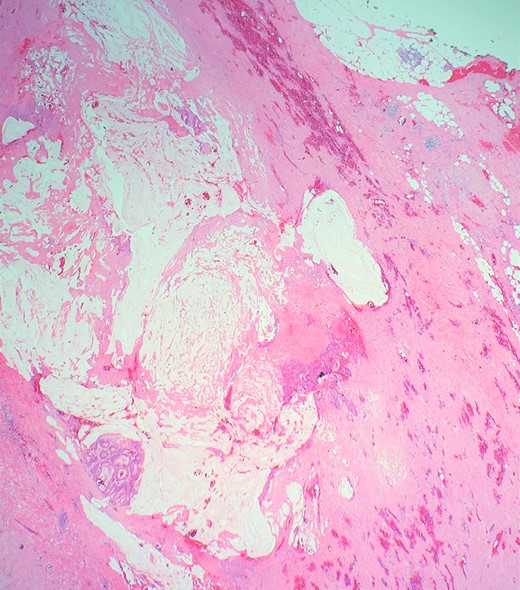

The cecum measures 8 × 6 cm and appendix is dilated and measures 7 cm × 2 cm. The mucosa at the appendicular orifice demonstrates a polypoid appearing mass measuring 3.2 × 1.5 cm (Fig. 3). Grossly the mass extends throughout the appendix and measures approximately 7.7 cm × 2 cm. The distal aspect was hemorrhagic and ragged, with an opened ragged defect measuring 1 cm in greatest dimension (Fig. 4). The majority of the appendicular serosa was tan and smooth, with scattered red areas. Grossly, the tumor is 1.5 cm from the mesenteric margin. Multiple lymph node candidates are identified. One lymph node candidate measures up to 5 mm and is 4 mm from the mesenteric margin.

A longitudinal cross section of the appendix, adenoma at appendiceal orifice on left, hemorrhagic tip rupture on right.